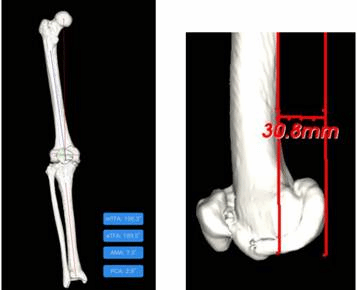

耿硕医生考虑到阿姨的年龄及身体状况,此时精准手术及快速康复的需求变得更为重要。出于这两个需求的考量,耿硕医生为吴阿姨进行了个性化的术前规划。术前利用AI智能规划技术精准定位截骨位置,在减少手术创伤的同时缩短了手术时间,还可提前预演截骨操作及假体置换后的效果;通过IPSI(Intelligent Patient-specific instrumentation)的使用,解决了传统的截骨器械内外翻角度固定、选择有限、股骨开髓带来的常规创伤的问题,可针对患者自己的内外翻角度定制更适合患者的个性化手术模式,无需股骨开髓减少出血量更适合老年患者。搭配集采中的最新一代膝关节系统Attune假体的植入,更高效的呈现了科技与高质量假体的术后效果,利于患者术后快速康复及提供给患者更好的术后体验。

术前:

(图一)通过AIJOINT进行术前精准定位

(图四)带位点标记的患者膝关节3D模型